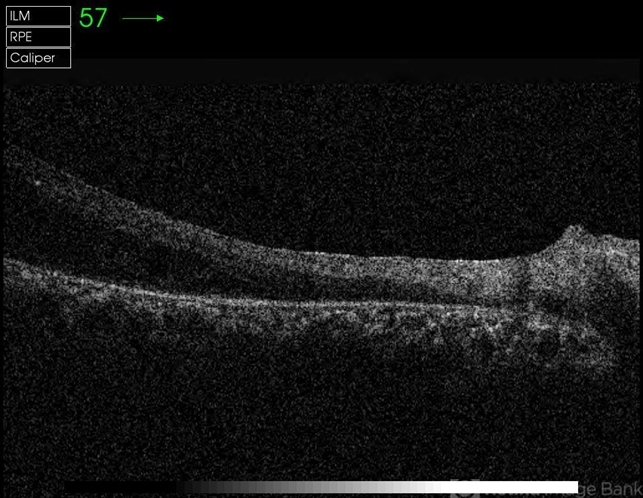

- optical coherence tomography (OCT), traction retinoschisis

- OCT image of the right eye of a 48-year-old man with advanced FEVR, traction retinoschisis and visual acuity of 20/100.